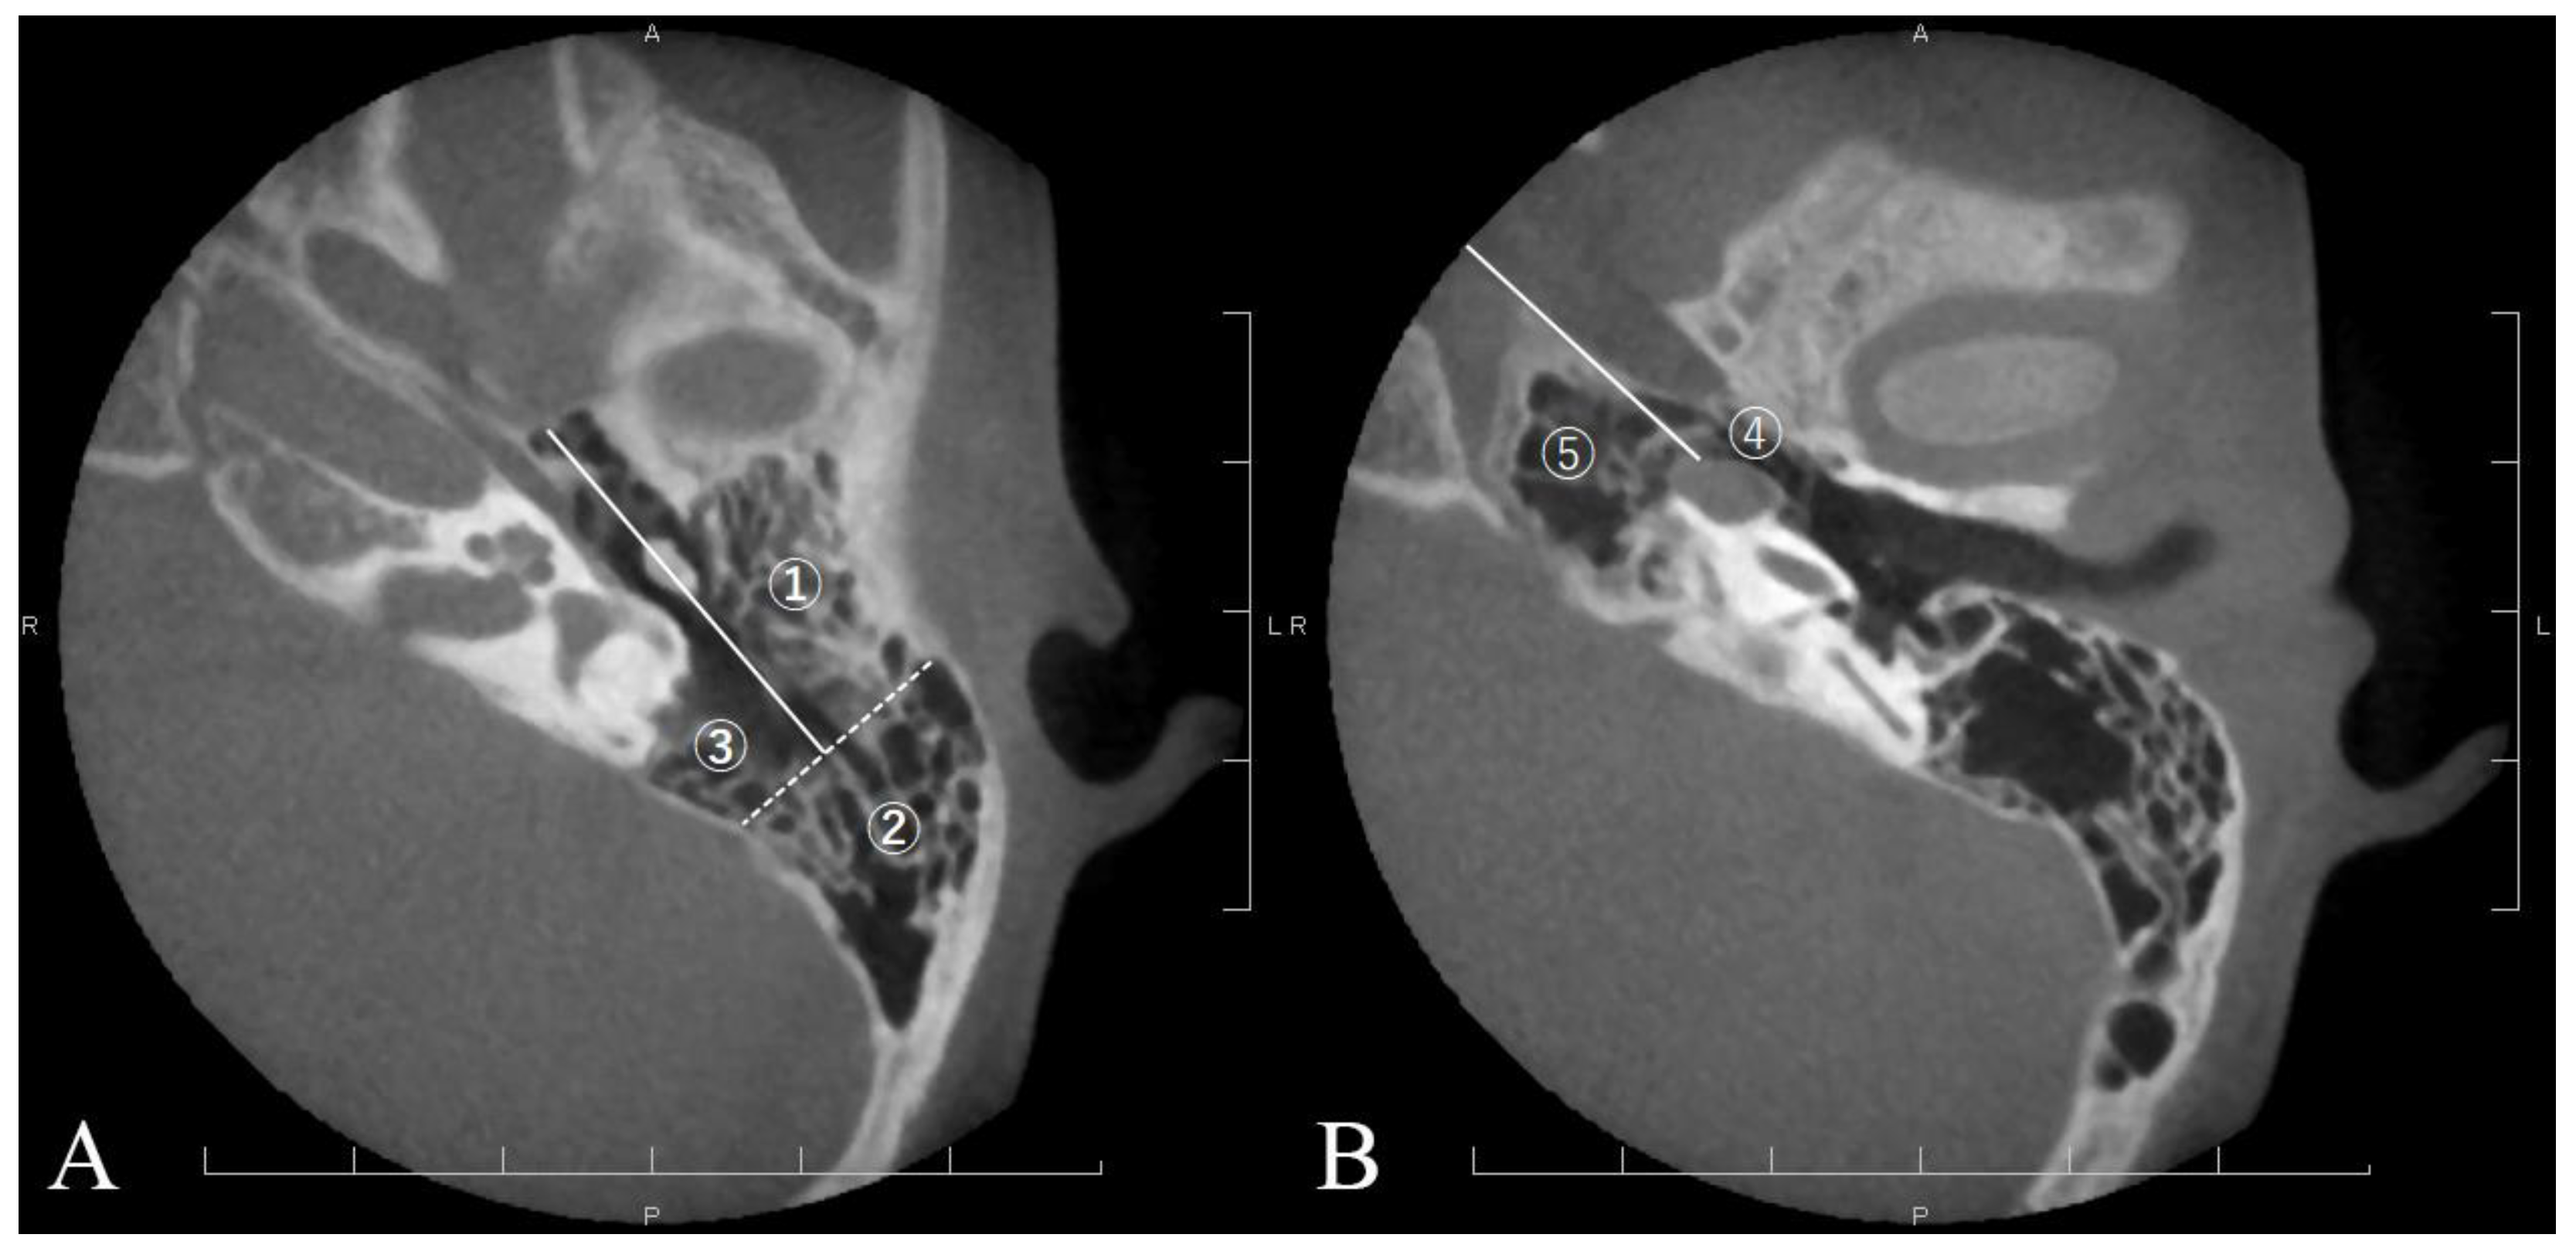

| ① | Anterolateral area of peri-antrum | 26/29 | (89.7%) | 26/29 | (89.7%) | 1.000 |

| ② | Posterolateral area of peri-antrum | 18/29 | (62.1%) | 26/29 | (89.7%) | 0.014 |

| ③ | Medial area of peri-antrum | 17/29 | (58.6%) | 28/29 | (96.6%) | <0.001 |

| ④ | Peritubal area | 16/29 | (55.2%) | 25/29 | (86.2%) | 0.009 |

| ⑤ | Petrous apex area | 7/29 | (24.1%) | 15/29 | (51.7%) | 0.030 |

| Acquired cholesteatoma (n = 34) | ||||||

| ① | Anterolateral area of peri-antrum | 21/34 | (61.8%) | 21/34 | (61.8%) | 1.000 |

| ② | Posterolateral area of peri-antrum | 24/34 | (70.6%) | 23/34 | (67.6%) | 1.000 |

| ③ | Medial area of peri-antrum | 11/34 | (32.4%) | 23/34 | (67.6%) | 0.007 |

| ④ | Peritubal area | 13/34 | (38.2%) | 24/34 | (70.6%) | 0.014 |

| ⑤ | Petrous apex area | 0/34 | (0%) | 3/34 | (8.8%) | 0.239 |